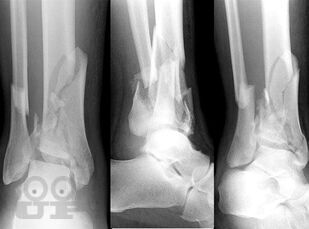

Учебно-методическое пособие содержит необходимую информацию для врачей по вопросам профилактики и лечения последствий тяжелых повреждений области голеностопного сустава. В Пособии представлены условия развития тяжелых статико-динамических осложнений при травмах голеностопного сустава, особенности осложнений при последствиях переломов дистального суставного отдела костей голени. Особое внимание уделено механизму развития посттравматического плоскостопия при повреждениях области голеностопного сустава.

В пособии обобщен более, чем 30-летний опыт лечения пациентов с последствиями тяжелых повреждений области голеностопного сустава.